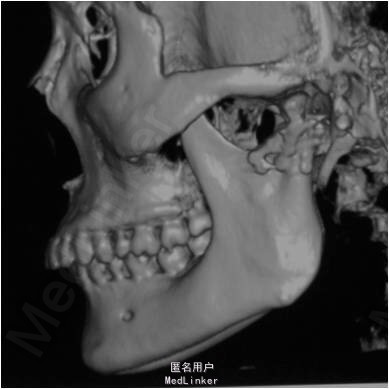

颏部可见擦伤,其余部位未见明显外伤。曲面断层和CT提示,左侧髁突骨质连续性中断

左侧髁突骨折 全麻下切开复位内固定